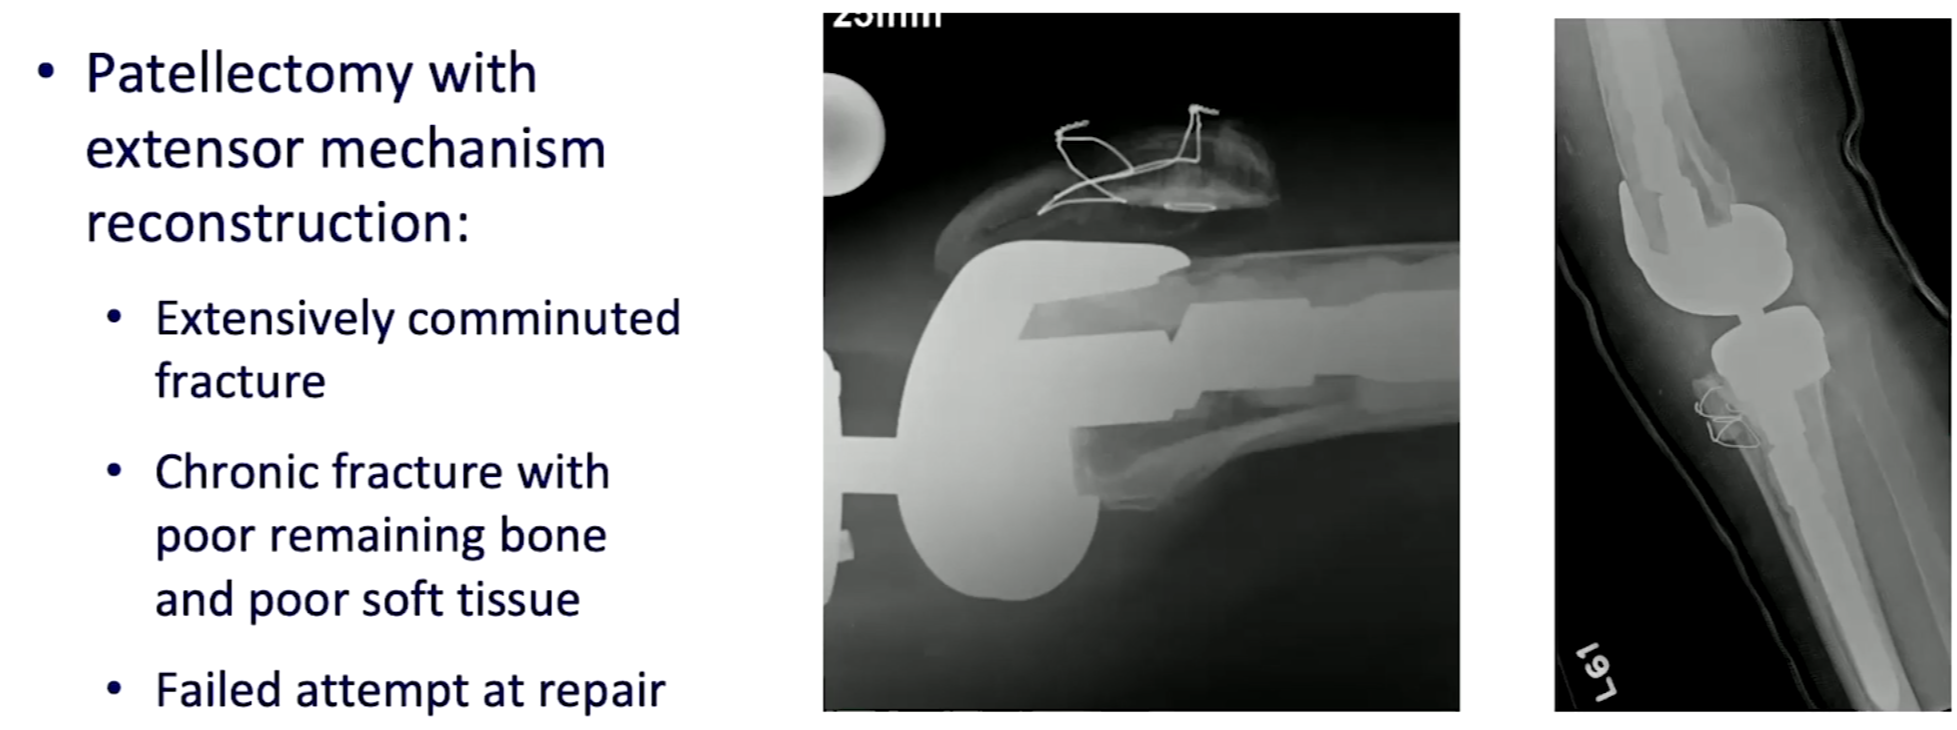

심하게 골절이 있는 경우는 슬개골을 재거하는 것 까지 생각해야 합니다.

Type III의 경우 골질의 양에 따라 두개로 선택지를 나누어 치료를 할 수 있습니다.